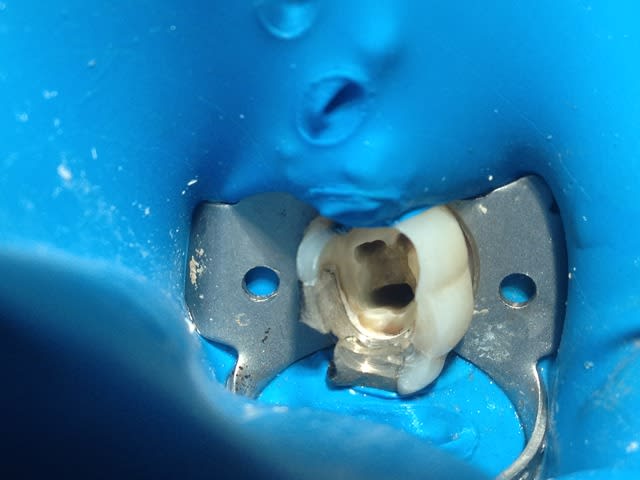

Traitement radiculaire sur molaire faite selon les données acquises de la science (89,92 euros) (1 heure de boulot)

Coût consommable: allez, 10 euros, frais de fonctionnement: 200 euros, prestation: -120,08 euros